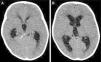

Se presenta el caso de un niño de 16 meses nacido en España, atendido en urgencias por somnolencia desde hace 8 h en el contexto de fiebre y tos de 5 días de evolución. El paciente había presentado 3 meses antes una adenitis cervical con mala respuesta a la antibioterapia, seguida de tos persistente en accesos, sin otros antecedentes de interés. En la exploración física destaca una disminución del nivel de consciencia (escala de coma de Glasgow, 12 puntos), alteración de la mirada conjugada y signos meníngeos positivos. La analítica de sangre presenta 11,4×103/μl leucocitos (39,1% linfocitos; 17,8% monocitos; 41,8% segmentados) y PCR 5,3mg/dl, con resto de bioquímica normal. La tomografía computarizada craneal muestra hidrocefalia tricameral no comunicante, con una imagen hiperdensa obstruyendo el acueducto de Silvio, compatible con gliosis reactiva secundaria a exudado inflamatorio (fig. 1). Ante el cuadro de hipertensión intracraneal con deterioro neurológico progresivo, se coloca de urgencia un drenaje ventricular externo. El LCR ventricular presenta una bioquímica normal (glucosa 83mg/dl, proteínas 20mg/dl), sin leucocitos ni gérmenes en la tinción de Gram. Pese a ello, dado el antecedente de adenoflemón de curso tórpido, la meningitis con hidrocefalia aguda y la linfomonocitosis se sospecha una meningitis tuberculosa y se inicia tratamiento empírico con vancomicina, cefotaxima y 4 tuberculostáticos (isoniazida, rifampicina, pirazinamida y etambutol), así como dexametasona. Tras la intervención se recoge muestra de secreciones respiratorias por tubo endotraqueal, con radiografía de tórax normal pero PCR positiva para micobacterias al 4.° día de ingreso. El diagnóstico de meningitis tuberculosa se confirma posteriormente mediante PCR de LCR a los 7 días, con Ziehl-Neelsen y cultivos para micobacterias negativos, tanto en secreciones respiratorias como en LCR. La resonancia magnética de control muestra una disminución del tamaño ventricular y la estenosis del extremo distal del acueducto de Silvio (fig. 2). Al tercer día se coloca una derivación ventrículo-peritoneal, completando 2 meses de tratamiento con 4 fármacos y 12 meses de isoniacida y rifampicina, con controles posteriores de RM con resolución de la hidrocefalia y válvula funcionante, persistiendo signos de flujo hiperdinámico a nivel del acueducto de Silvio. En la actualidad presenta un desarrollo psicomotor normal para la edad.